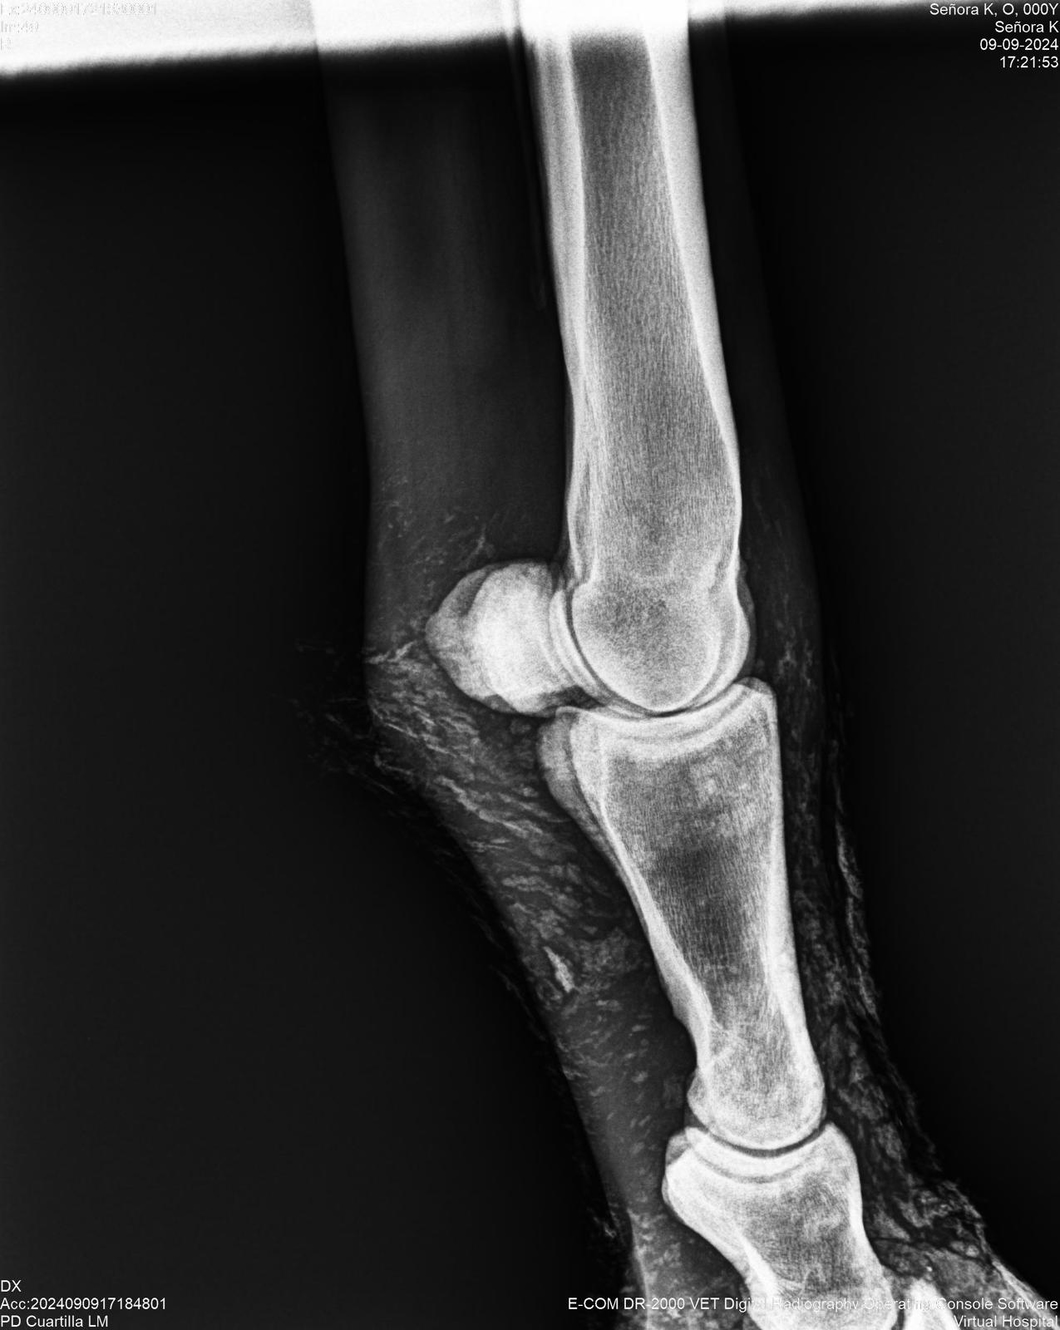

LOTE 44, SEÑORA K

Identificador: #291147-

Generacion 2022